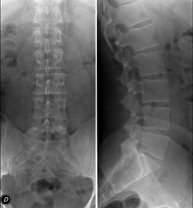

Tècnica que usa els raigs X a través de la qual s'obtenen imatges de la columna dorsal per al seu estudi. Indicacions: traumatisme, mal d'esquena. - RX Columna lumbar

Tècnica que usa els raigs X a través de la qual s'obtenen imatges de la columna lumbar per al seu estudi. Indicacions: ciàtica, traumatisme, dolor lumbar. - RX Sacre-còccix

Tècnica que usa els raigs X a través de la qual s'obtenen imatges de tota la columna vertebral per al seu estudi, amb la valoració especialment de la presència d'escoliosi i dismetries pèlviques.